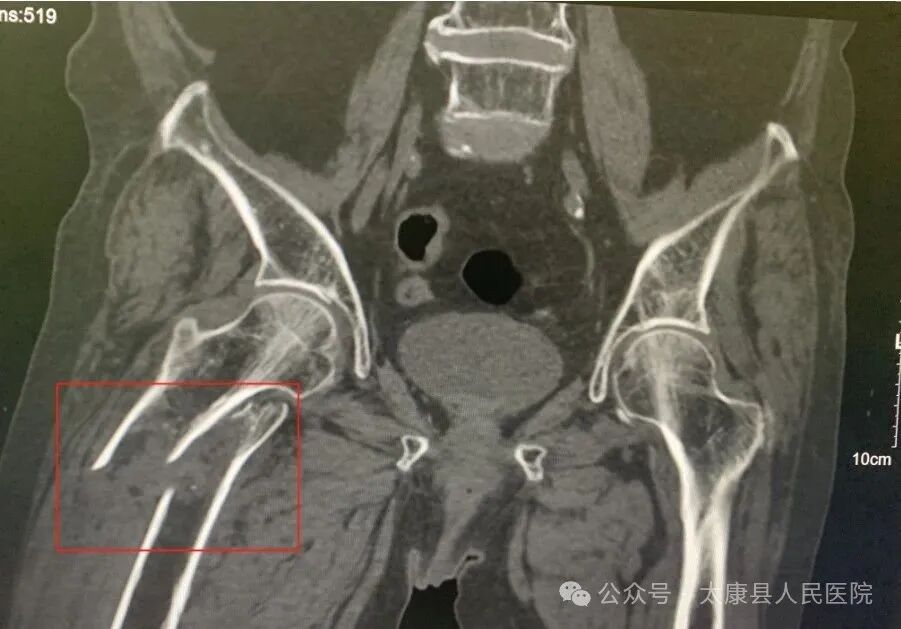

近日,97岁高龄的刘奶奶在家不慎摔倒后,剧烈的右髋疼痛让她瞬间失去行动能力。辗转多家医院因手术风险过高被拒后,家属带着最后希望来到太康县人民医院骨科二病区。经骨科二团队详细检查,确诊为死亡率极高的右股骨粗隆间骨折合并肺动脉高压。

一场多学科联合救治战役迅速打响:麻醉科量身定制精准麻醉套餐 ;心内科24小时动态监测心肺功能; ICU提前介入制定术后管理方案。经过48小时紧锣密鼓的术前准备,在王保华主任医师的主刀下,手术团队凭借毫米级精准操作,仅用100毫升出血量完成骨折复位内固定,最大程度减少组织损伤。